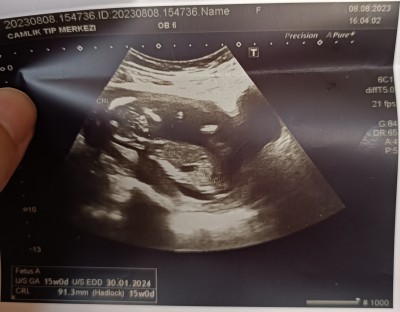

Teyzeleri cinsiyet tahmini yapar mısınız 15+0

Sizce nedir bilen varsa yazabilir mi?

Yapıyorum erkek

Neye göre erkek dediniz acaba:)

Ay ben hıssıyattan soyledım anlamam yoksa ama dedıgımın tersı cıkar hep

Hiçbir şey anlaşılmıyor doktor bişey demedi mi

Tahminde bulundu ama söylemedi malesef haftaya tekrar çağırdı

Onu da söylemedi boşuna tahmin olur haftaya net belli olur dedi ısrar ettim ama söylemedi

Pipi yok gibi düz görünüyor kız gibi sağlıkla gelsin inşallah

Ben kız diyorum Dr ne tahminde bulundu

Kız bence Allah gönlüne göre versin İŞALLAH

Kiz gibi geldi

Kız gibi geldi ilk çocuk mu

Bence erkek cnm